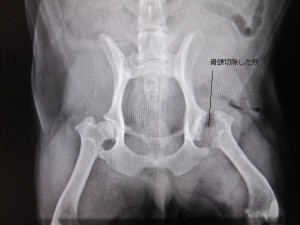

術後

術後のレントゲンです。

左大腿骨頭を切除しました。